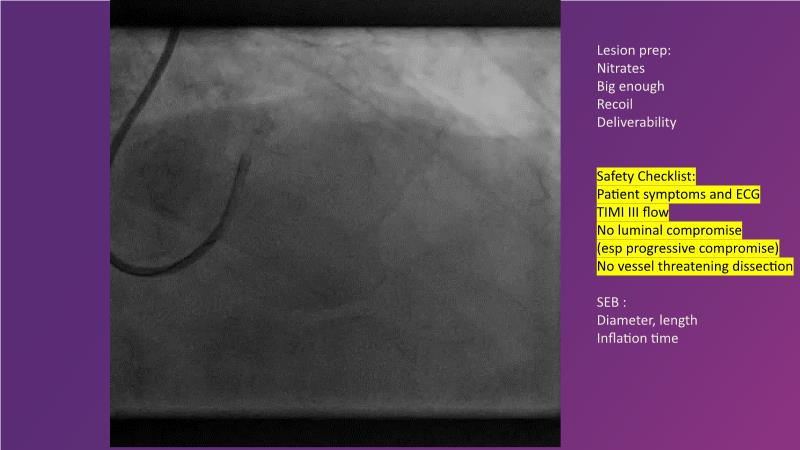

Explore the latest trends in percutaneous coronary intervention (PCI) in this session, focusing on stentless PCI and the role of sustained limus release technology. Join the discussion on how sustained limus release can expand the indications for drug-eluting balloons (DEB) and minimize the use of metal stents, gain insights into the importance of vessel preparation and learn which tools to utilize in specific scenarios.

- To discuss how sustained limus release technology can broaden DEB indications and reduce metal

- To learn about the importance of vessel preparation and which tool to use when

- To review clinical scenarios when a stent is not required